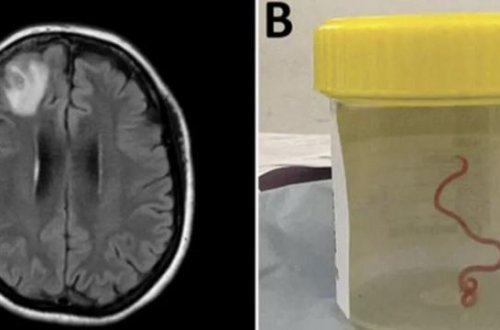

Gölməçələrdə və çaylarda tapılan qurd şizofreniya xəstəliyinin müalicəsində istifadə edilə bilər